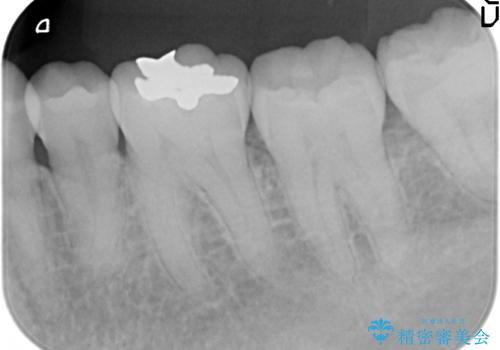

セラミックインレー しみる奥歯の治療

- 左下の奥歯がしみるので診て欲しいといらっしゃった方の症例です。

左下6の古い銀歯及び虫歯を除去し、セラミックインレーによる修復を行いました。

当院のセラミックインレーはemaxという強度と審美性に優れた材料を使用しています。

またプレス方式でインレーを製作しているため、削り出しで製作するCADCAMより優れた適合性も持ち合わせており、虫歯が再発しにくい修復物です。